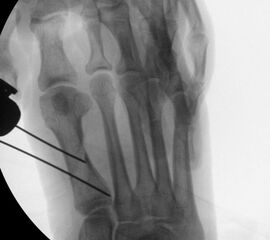

• Bildverstärker für intraoperative Kontrollaufnahmen 3.

• Bildverstärker.

• Positionierung des Bildverstärkers im 90° Winkel zur Fußlängsachse (Abbildung 4).

• Röntgenkontrollen (Vorfuß d.p. und seitlich) postoperativ ohne Belastung. Weitere Kontrollen erfolgen 6 Wochen, sowie 3, 6 und 12 Monate jeweils unter Belastung.